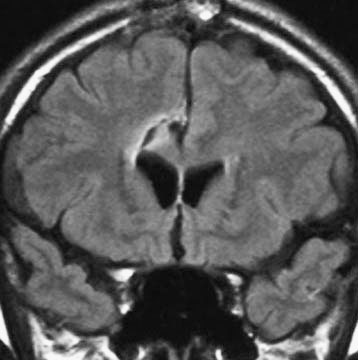

軽度の左下肢の麻痺で発症した50代の患者さんです。一見,かつてのグリオマトーシス gliomatosis あるいは diffuse hemispheric glioma WHO grade 4 のように見える非常に広範囲な病変です。しかし,病理診断は 星細胞腫 IDH mutant WHO grade 2でした。

放射線治療によく反応し,片麻痺は消失して,画像上の腫瘍高信号もほぼ消失しています。